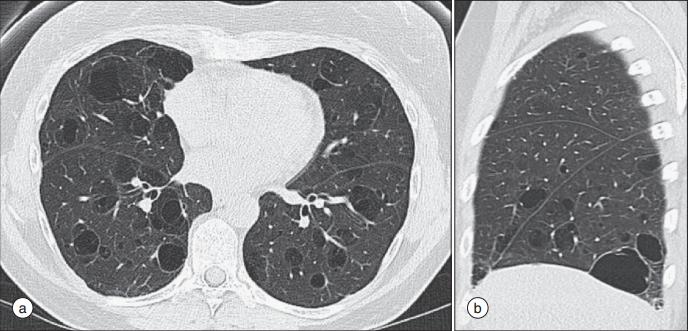

4,肺部

10%-20%的原发性干燥综合征患者存在具有临床意义的肺病变。主要症状是咳嗽或呼吸困难。病理上是支气管扩张、间质性肺病等等。

由于气道分泌能力、清除能力下降,从而导致反复支气管炎,即表现出持续干咳、呼吸困难。高分辨率CT成像可能显示有支气管气道增厚、支气管扩张、小叶中央结节、网状或网状结节性浸润以及空气潴留。

干燥病人的肺囊性病变